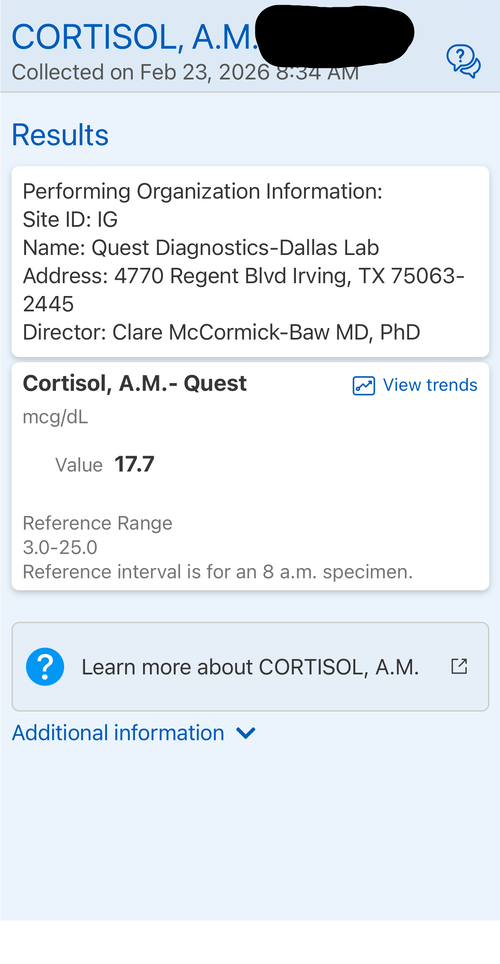

Introduction: The goal of this protocol is to hit my genetic potential. This is my first time experimenting with any pharmaceuticals. I am considering this based on my genetic potential allowing for more growth and the fact I need to take quick action if I want to hit my genetic target before my growth plates fuse. I may use an aromatase inhibitor but considering the fact my prior experience with pharmaceuticals is none I am fearful of having a “stack” of drugs and not having the resources to operate it well. I want to gain significant height in the most simple and low risk way possible. I will attach some blood work on my IGF-1, Cortisol, Testosterone and I have a bone age X-Ray which indicates my plates are open but estrogen exposure is starting the closure process. I will also attach a growth chart.

Introduction: The goal of this protocol is to hit my genetic potential. This is my first time experimenting with any pharmaceuticals. I am considering this based on my genetic potential allowing for more growth and the fact I need to take quick action if I want to hit my genetic target before my growth plates fuse. I may use an aromatase inhibitor but considering the fact my prior experience with pharmaceuticals is none I am fearful of having a “stack” of drugs and not having the resources to operate it well. I want to gain significant height in the most simple and low risk way possible. I will attach some blood work on my IGF-1, Cortisol, Testosterone and I have a bone age X-Ray which indicates my plates are open but estrogen exposure is starting the closure process. I will also attach a growth chart.